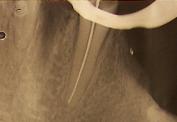

El seguimiento radiográfico es imprescindible a lo largo de una endodoncia, sólo de esta manera se pueden prever posibles complicaciones y controlar paso a paso el procedimiento.

Esta es una fase muy importante que además condiciona las restantes y de la que depende en gran medida el éxito de la endodoncia. Consiste en medir la longitud exacta de cada conducto tomando como referencia alguna parte de la corona del diente. Clásicamente se hace por medio de una radiografía, habiendo introducido en el diente una lima endodoncia a modo de referencia. Hoy en día es muy importante contrastar esa medida de manera mucho más exacta con el uso de localizadores electrónicos de ápice.

Una vez se ha realizado la limpieza y conformación, se procede al secado mediante puntas de papel y al cierre hermético y tridimensional de cada conducto. Esto se realiza mediante un material llamado "gutapercha",en forma de conos, usado universalmente en endodoncia. Previamente se debe comprobar radiográficamente la longitud y el ajuste del cono principal.

La técnica más extendida consiste en ir sellando el conducto mediante puntas de este material que ajustan a la longitud exacta del conducto (aproximadamente a medio milímetro del final), de esta manera se van aplicando una tras otra y presionando lateralmente hasta que el conducto se ha obturado completamente. Como agente de unión se emplea un cemento específico para endodoncia. Existen también otras técnicas donde la gutapercha se calienta y se compacta verticalmente.

Es muy importante que el conducto quede totalmente obturado a la longitud correcta (de 1 mm a 0,5 mm del final). El material no debe quedar a menos distancia ni pasarse de esta longitud para obtener las mayores posibilidades de éxito.